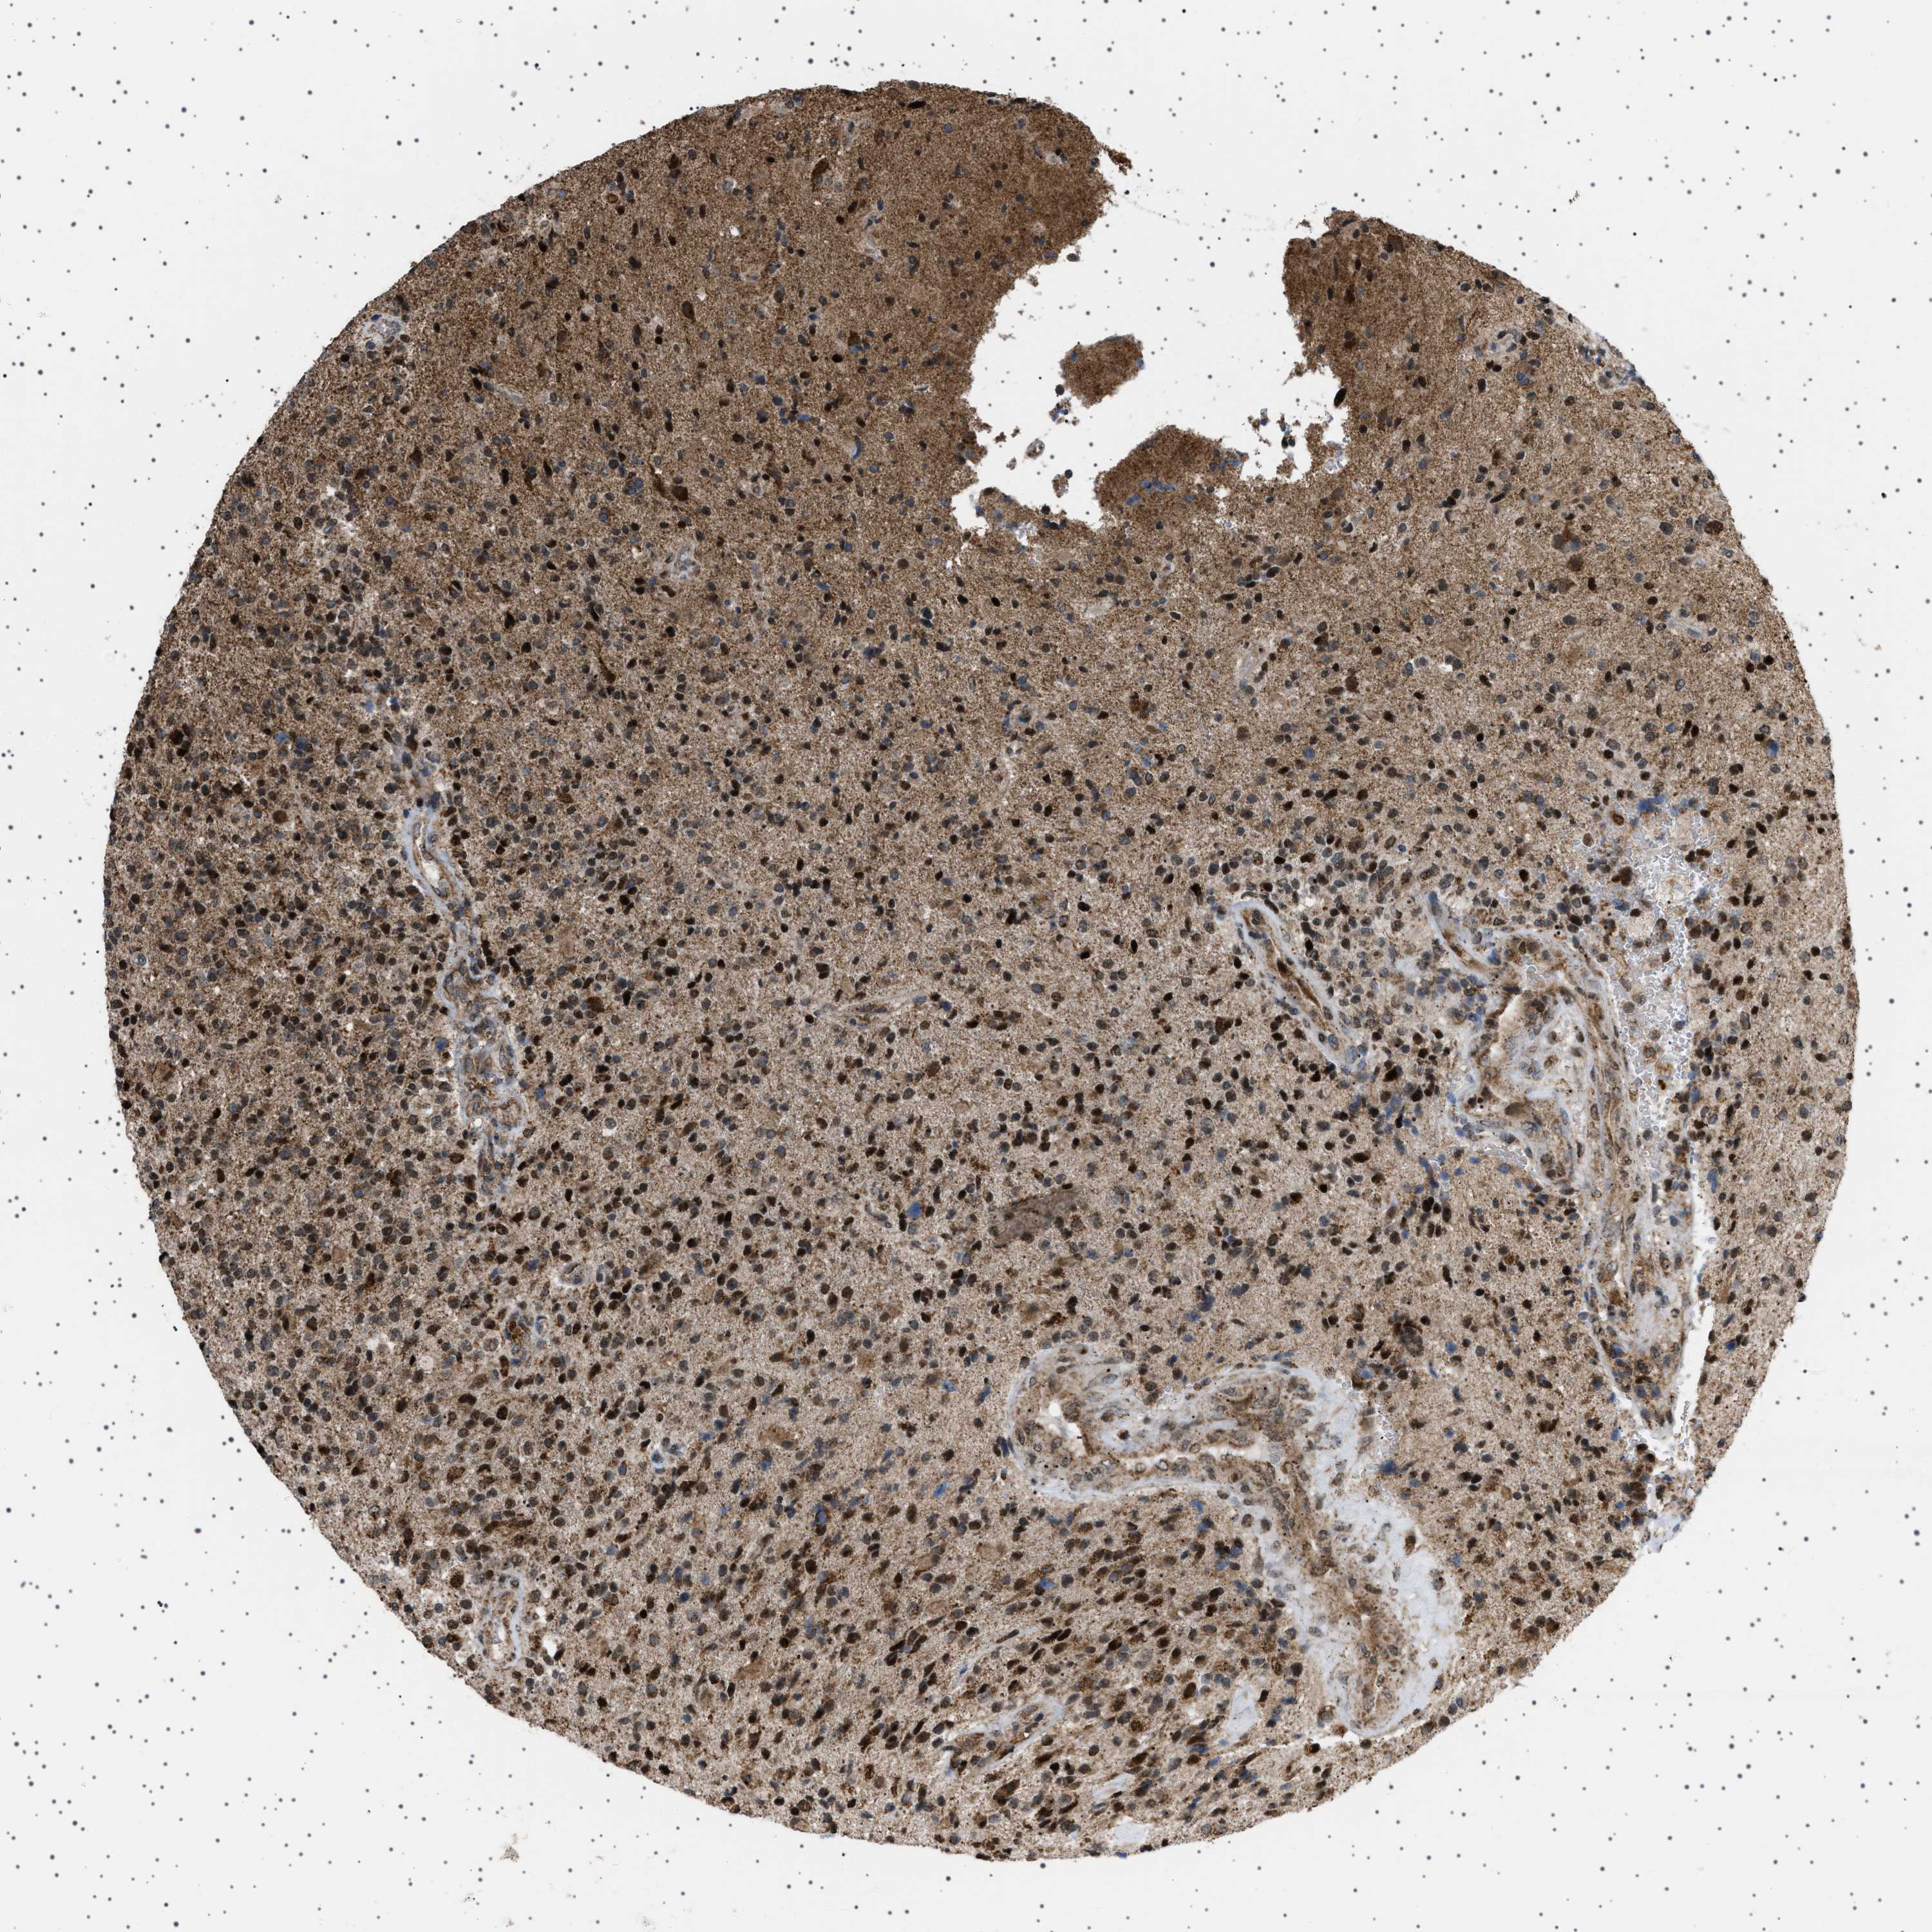

GLIOMA - Protein expressioni

A mouse-over function shows sample information and annotation data. Click on an image to view it in a full screen mode. Samples can be filtered based on level of antibody staining by selecting one or several of the following categories: high, medium, low and not detected. The assay and annotation is described here.

Note that samples used for immunohistochemistry by the Human Protein Atlas do not correspond to samples in the TCGA dataset.

Antibody stainingi

Antibody staining in the annotated cell types in the current human tissue is reported as not detected, low, medium, or high, based on conventional immunohistochemistry profiling in selected tissues. This score is based on the combination of the staining intensity and fraction of stained cells.

Each image is clickable and will lead to virtual microscopy that enables deeper exploration of all samples and also displays staining intensity scores, fraction scores and subcellular localization as well as patient and tissue information for each sample.

Antibody HPA017214

Staining

High

Medium

Low

Not detected

Intensity

Strong

Moderate

Weak

Negative

Quantity

>75%

75%-25%

<25%

None

Location

Nuclear

Cytoplasmic/membranous

Cytoplasmic/membranous,nuclear

Glioma, malignant, High grade

Glioma, malignant, Low grade